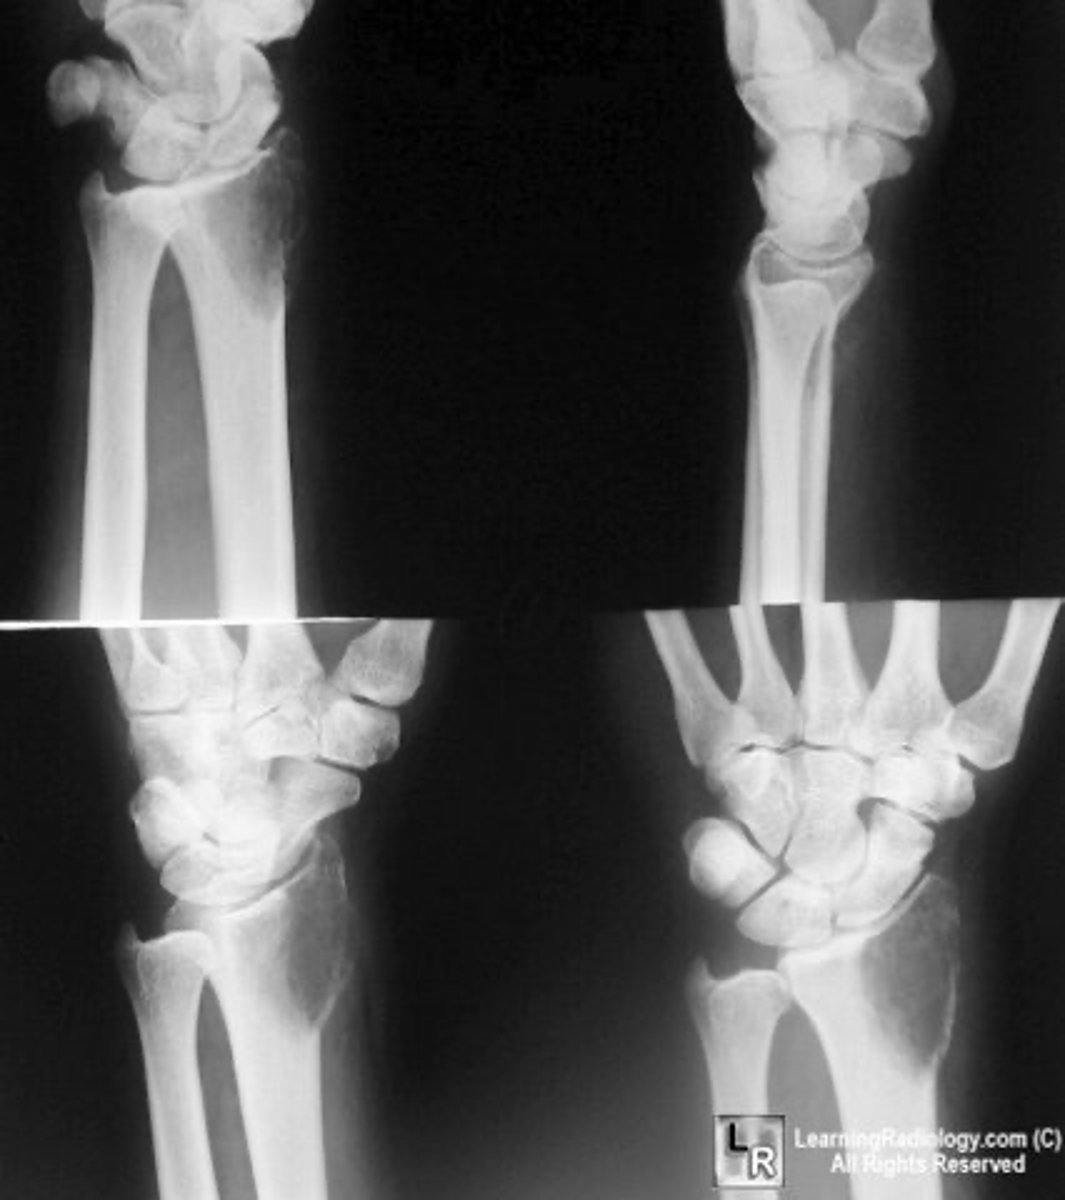

Vignette # 8

Sex: Female

Age: 82

Chief Complaint: Patient presents with sudden onset of low back pain while gardening. Patient reports feeling a sharp pain with movements and feels better with ice. Pain is rated an 8 out of 10 on the pain scale.

Objective Findings: No orthos were performed due to pain Diagnostic imaging: X-ray

1. List the radiographic signs you expect to see on the film. (Choose 3)

a. Ivory white vertebral body

b. Synostosis (fusion of two bones)

c. DDD

d. Fusiform shape (AAA)

e. Atherosclerotic plaquing

f. Dilation of abdominal aorta

g. Osteopenia (low bone density)

h. Anterior wedge deformity

DEXA

CT

Abdominal Ultrasound

2. Which tests would be used to diagnose this condition? (Choose 3)

a. DEXA(for osteoporosis)

b. MRI

c. CT

d. PET

e. CBC

f. Angiogram

g. Abdominal ultrasound

h. Alkaline phosphatase

Fit for elastic lumbar support

Adjust lumbar

Limit certain physical activities

3. List the treatments for this condition. (Choose 3)

a. Defer adjusting

b. Prescribe NSAIDs

c. Fit for elastic lumbar support

d. Adjust lumbar

e. Oncologist

f. Vascular surgeon

g. Surgical consult

h. Limit certain physical activities